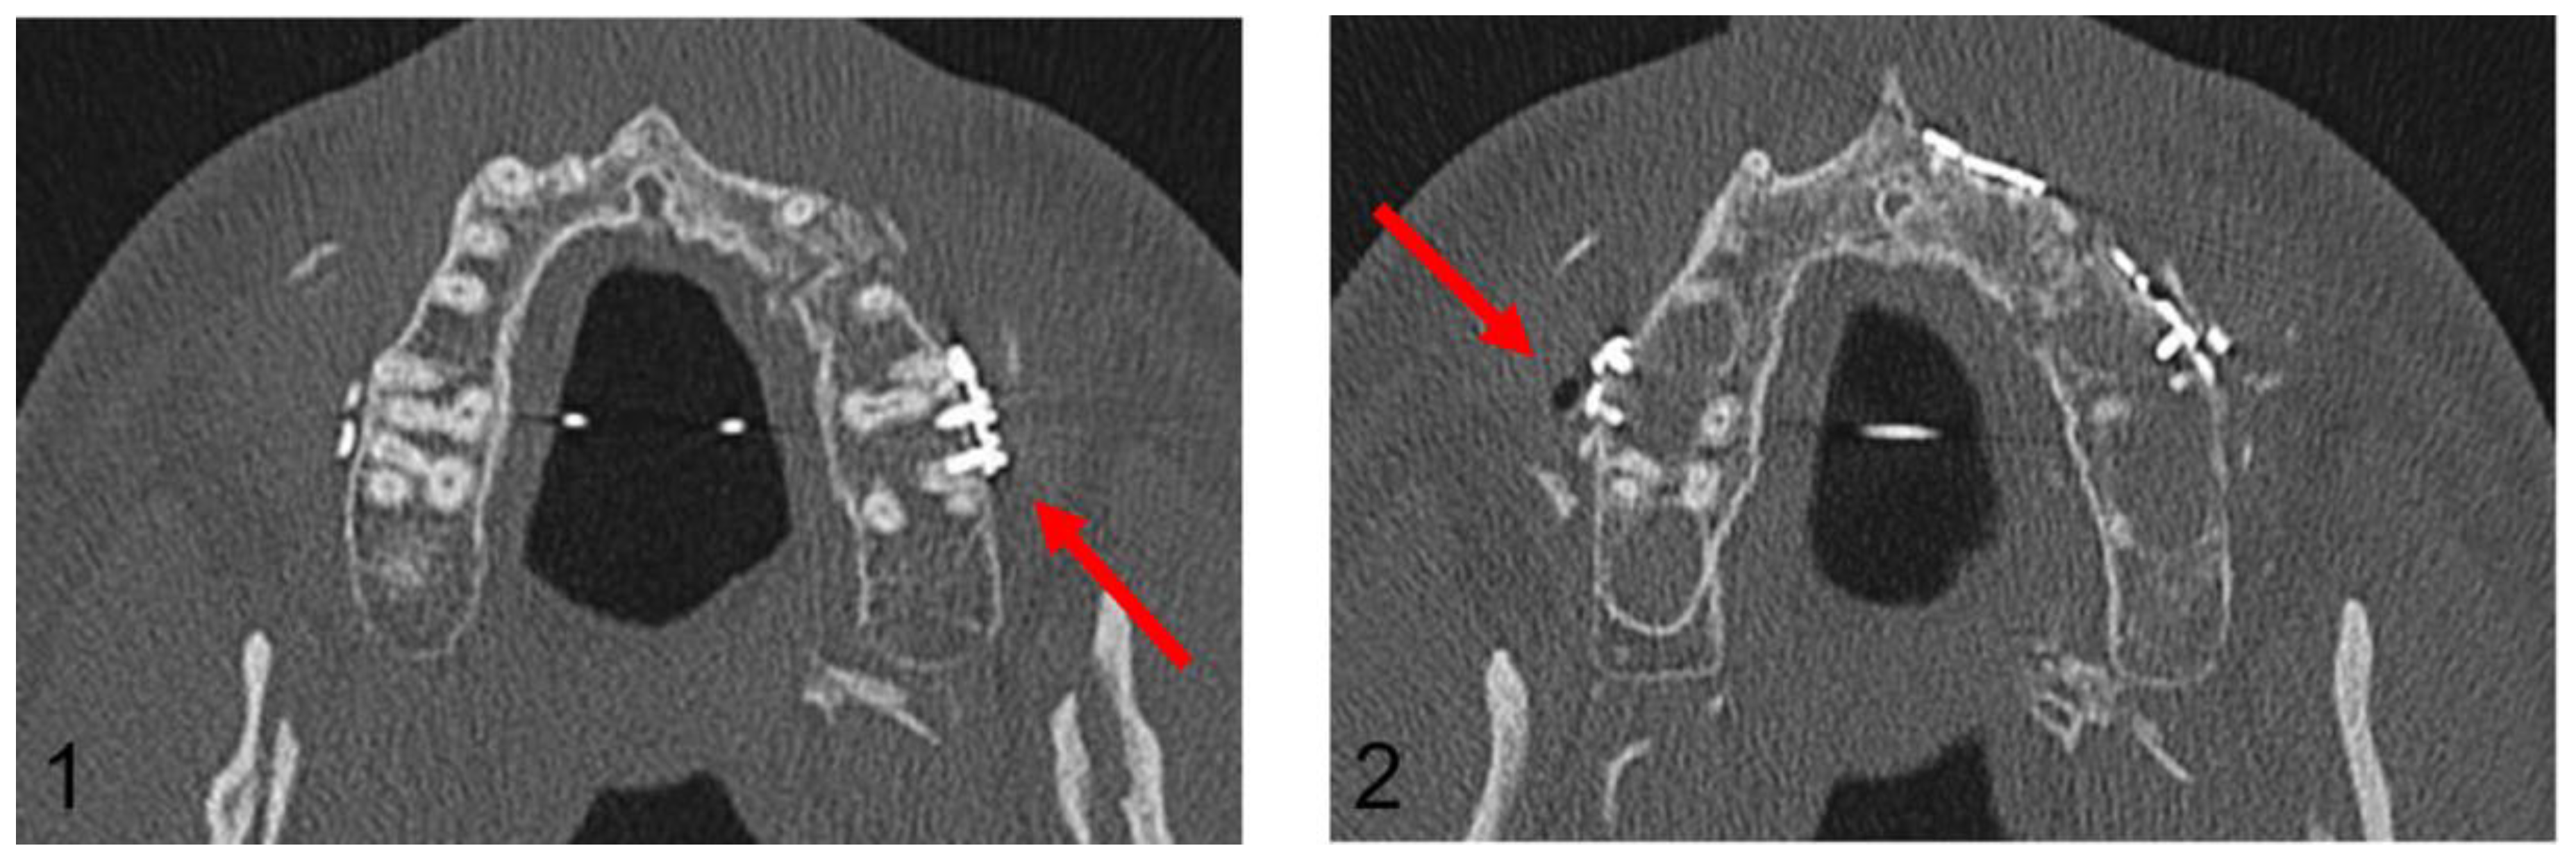

Figure 6.

Post-operative orthopantomogram after the conventional maxillary positioning, showing the projections of three osteosynthesis screws with the dental roots of the teeth 16 and 17 and the projections of four osteosynthesis screws with the dental roots of the teeth 26 and 27 (red arrows).

Figure 7.

Axial plane of post-operative CT scan. Image (1) shows an injury of the mesiobuccal tooth root of tooth 27, while in image (2), no root injury in the right maxillary molars is detected (red arrows).

In the Maxilla Conventional cohort, 94 radiological projections of osteosynthesis screws with the dental roots were detected in the post-operative OPG. In contrast, post-operative CT imaging detected only 10 dental root injuries. In the Maxilla PSI cohort, 64 radiological projections were detected; however, no dental root injury could be detected in post-operative CT imaging. In the mandible, a total of 106 projections in the premolar and molar region were recorded in the post-operative OPG, but only 12 root lesions were detected in post-operative CT scan.